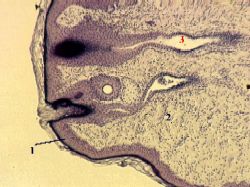

| 7. Препарат - сосок молочной железы. Окраска железным гематоксилином.

| Проис- хождение и состав | а) Сосок молочной железы - не что иное, как утолщение кожи.

б) В связи с этим, он имеет обычные слои кожи -

эпидермис (1) и дерму (2), включающую сосочковый и сетчатый слои.

в) Содержатся и другие обычные компоненты кожи:

сальные железы (но без волос; протоки желёз могут открываться в млечные протоки),

а в ареоле (околососковом кружке) – также потовые железы.

| Млечные протоки | В отношении долевых протоков (3) можно также добавить следующее:

в основании соска они ещё расширены (представляя собой продолжение млечных синусов),

а затем - суживаются, меняют тип эпителия (на многослойный плоский ороговевающий) и открываются на поверхности млечными отверстиями.